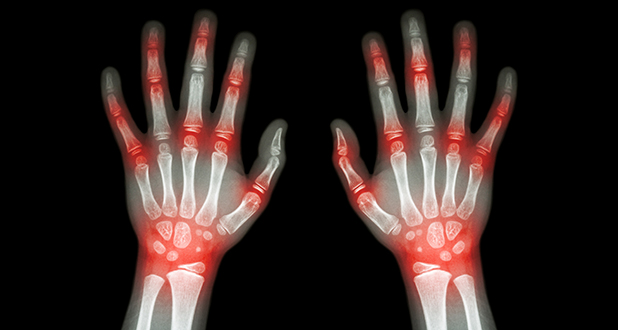

— рентгенографию и компьютерную томографию (КТ) для определения характера и распространенности патологического процесса;

— артрит — инфекционный или аутоиммунный, например, ревматоидный. В суставе развивается воспаление, сопровождающееся деструкцией и отеком. Сустав увеличивается, кожа над ним краснеет и становится горячей. Хроническое воспаление приводит к постоянным разрушениям, влияющим на форму сустава;

Врачи отмечают, что шишки на руках и деформация пальцев могут быть вызваны различными факторами. Одной из основных причин является артрит, воспалительное заболевание суставов, которое приводит к отеку и образованию узлов. Также часто встречается остеоартрит, связанный с износом хрящей, что может вызывать болевые ощущения и изменение формы пальцев. Врачи подчеркивают, что травмы, такие как вывихи или переломы, также могут привести к образованию шишек. Генетическая предрасположенность и возрастные изменения играют важную роль в развитии этих состояний. Регулярные физические нагрузки и правильное питание могут помочь в профилактике, однако при появлении симптомов необходимо обратиться к специалисту для диагностики и назначения лечения.